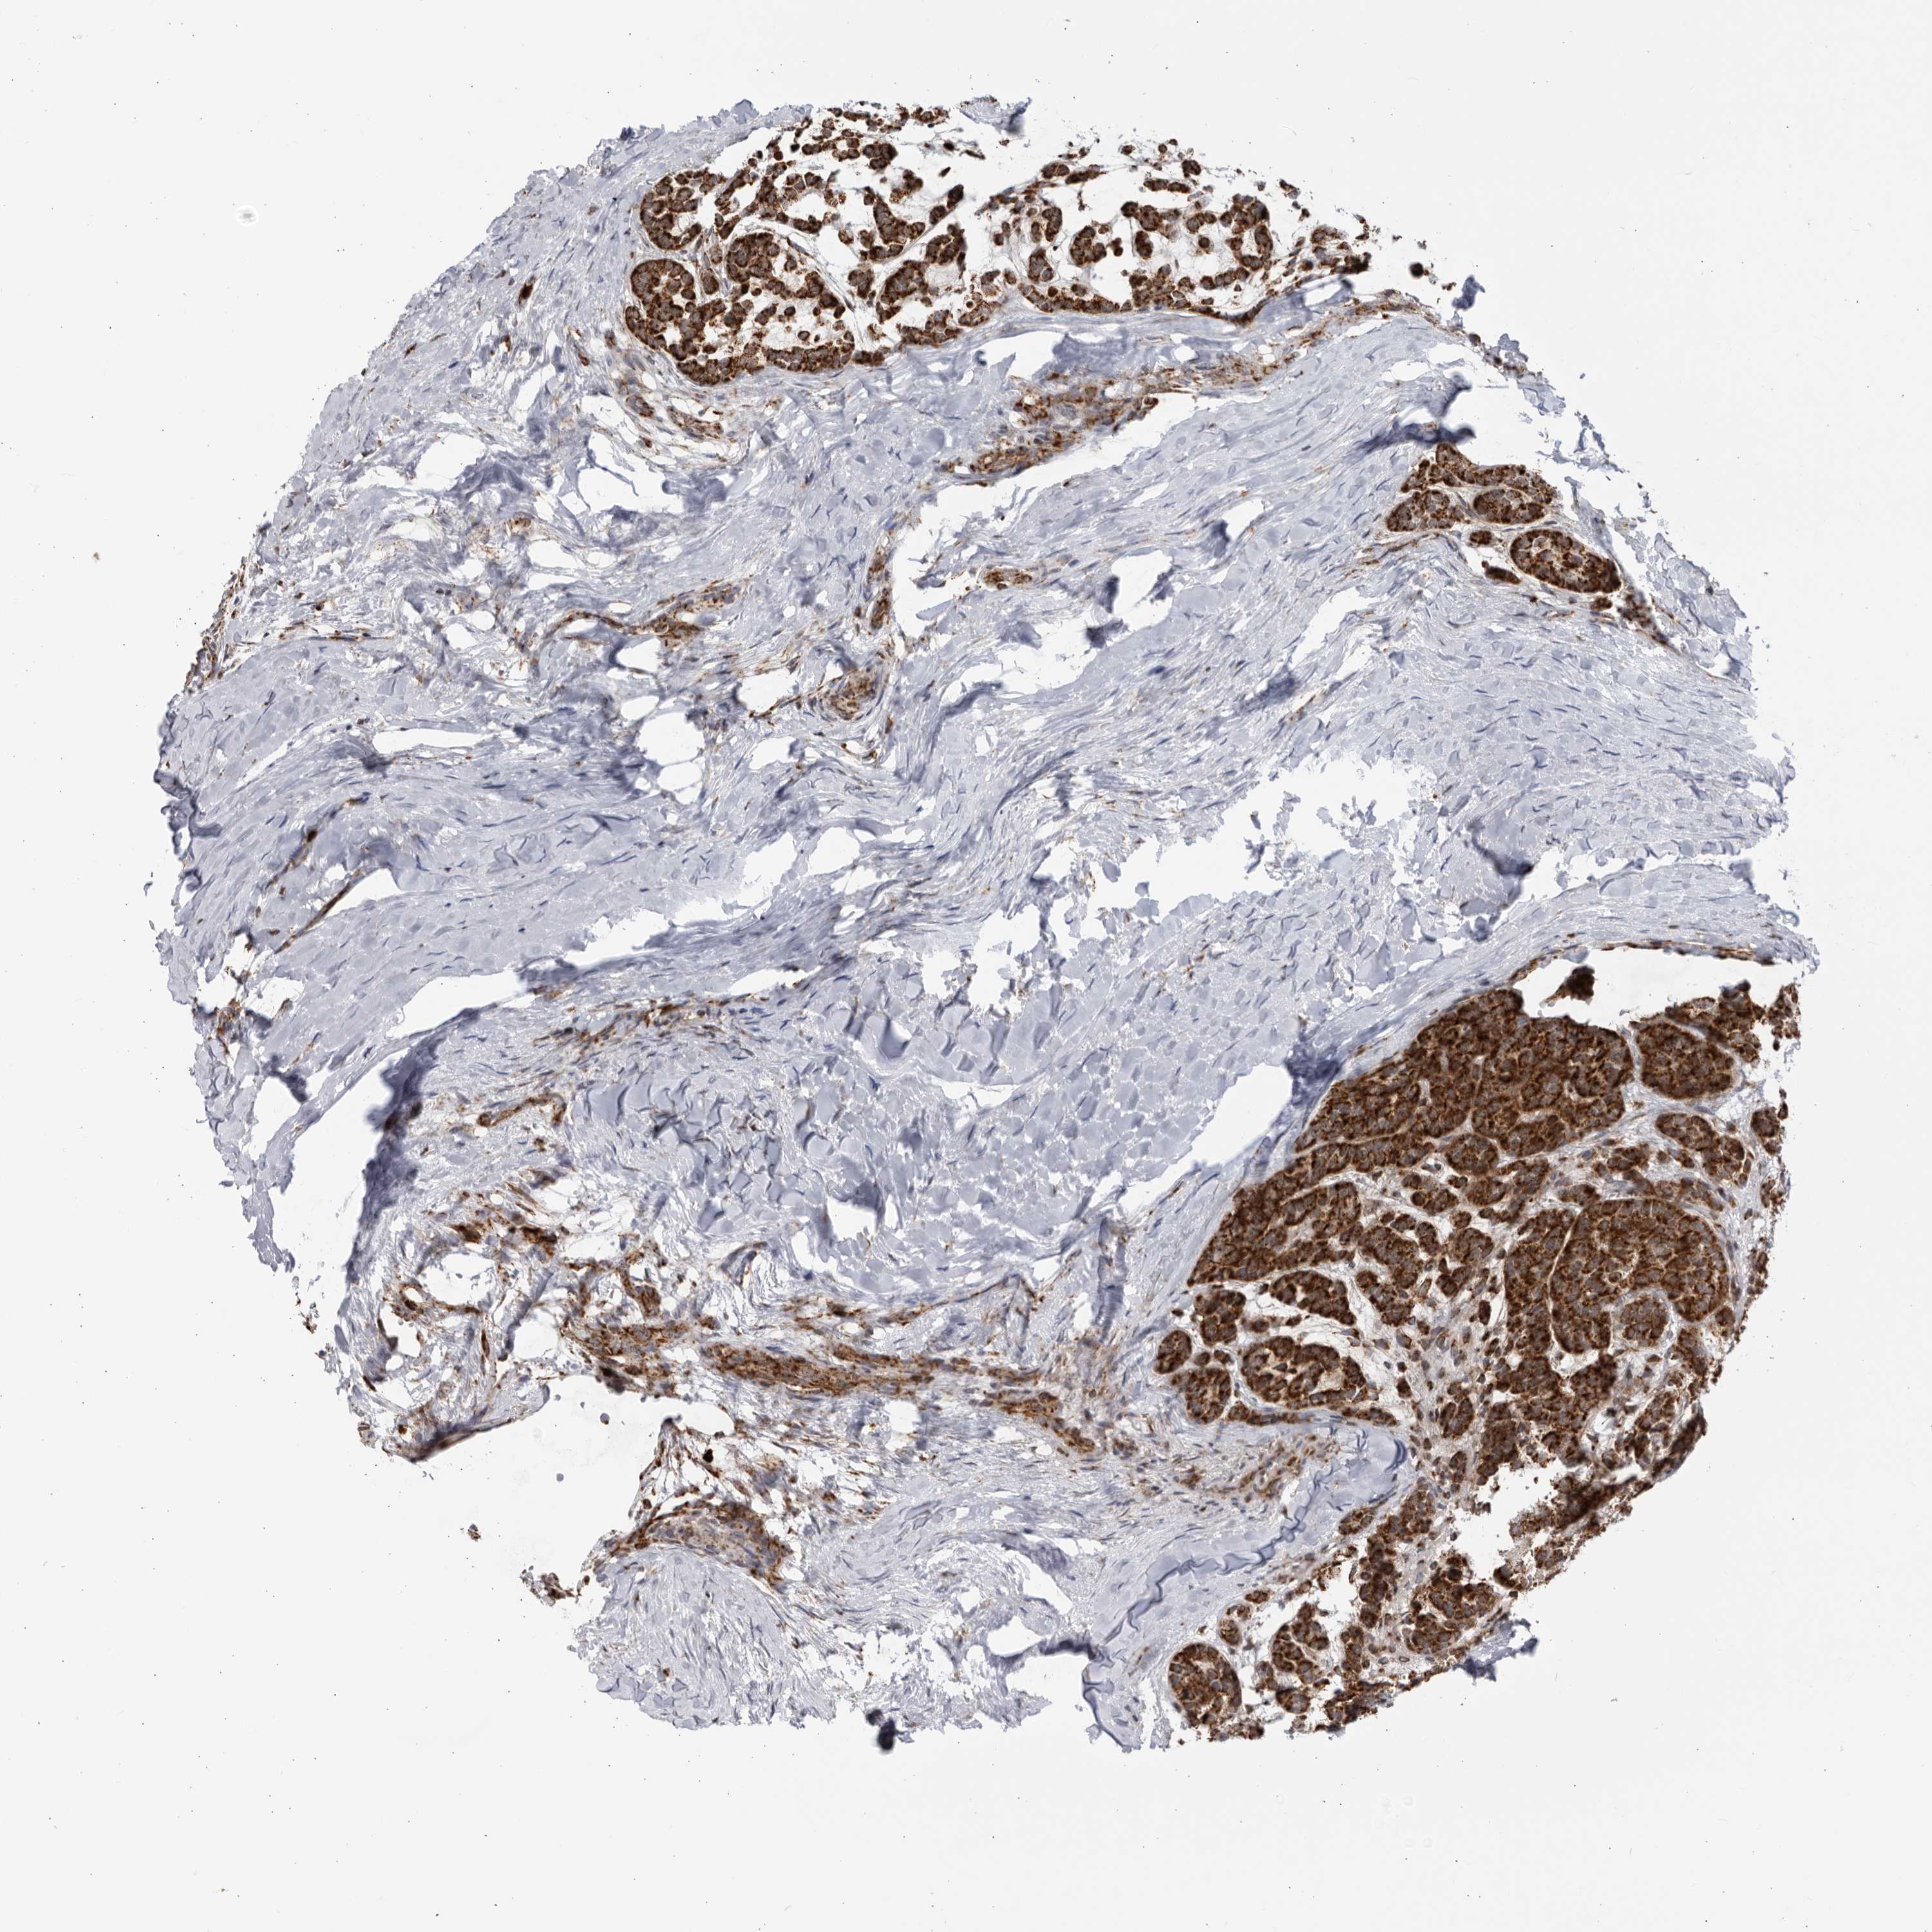

HEAD AND NECK CANCER - Protein expressioni

A mouse-over function shows sample information and annotation data. Click on an image to view it in a full screen mode. Samples can be filtered based on level of antibody staining by selecting one or several of the following categories: high, medium, low and not detected. The assay and annotation is described here.

Antibody stainingi

Antibody staining in the annotated cell types in the current human tissue is reported as not detected, low, medium, or high, based on conventional immunohistochemistry profiling in selected tissues. This score is based on the combination of the staining intensity and fraction of stained cells.

Each image is clickable and will lead to virtual microscopy that enables deeper exploration of all samples and also displays staining intensity scores, fraction scores and subcellular localization as well as patient and tissue information for each sample.

Antibody HPA028606

Staining

High

Medium

Low

Not detected

Intensity

Strong

Moderate

Weak

Negative

Quantity

>75%

75%-25%

<25%

None

Location

Nuclear

Cytoplasmic/membranous

Cytoplasmic/membranous,nuclear

Squamous cell carcinoma, NOS

Squamous cell carcinoma, metastatic, NOS

Adenocarcinoma, NOS

Adenoma, NOS